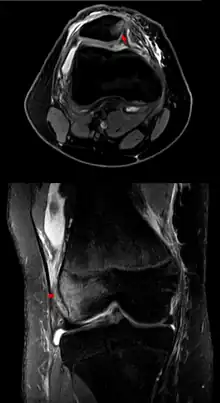

Luxating patella

A luxating patella, sometimes called a trick knee, is a condition in which the patella, or kneecap, dislocates or moves out of its normal location. It can be associated with damage to the anterior cruciate ligament.[1]

Patellar luxation is a common condition in dogs, particularly small and miniature breeds.[2] The condition usually becomes evident between the ages of 4 and 6 months. It can occur in cats, as well, especially domestic short-haired cats.[3]